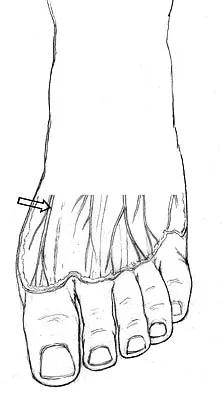

Because the patient shown in Figure 27 can no longer fit in shoes, treatment of the deformity should consist of

In local gigantism, a ray resection allows proper fitting of shoes. The ray resection narrows the foot and shortens the length. The foot may require further surgery with growth. Debulking, physeal arrest, and distal phalanx amputation are unlikely to be effective. Turra S, Santini S, Cagnoni G, Jacopetti T: Gigantism of the foot: Our experience in seven cases. J Pediatr Orthop 1998;18:337-345.